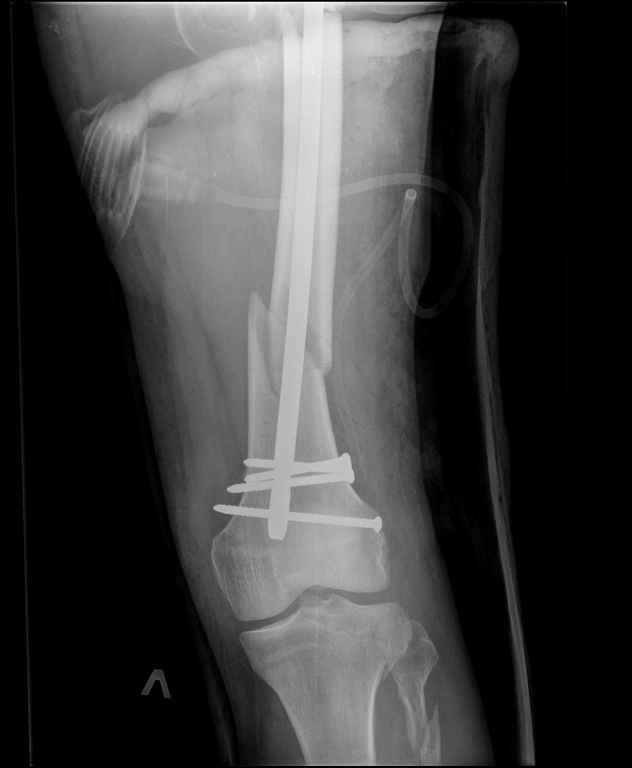

Ds: ТСТ. ЗЧМТ. СГМ. ЗТГК. О/фрагментарный перелом левого бедра. З/оскольчатый перелом с\3 левого плеча. Перелом левого локтевого отростка. З/перелом наружного мыщелка б/берцовой кости в/3 м/берцовой кости левой голени. при поступлении, ПХО раны левого бедра( рана 1х1см по наружной поверхности бедра в с/3) налажено скелетное вытяжение , и гипсовая лонгета на левую в/конечность. Находился в реанимации. 17.02.11 был прооперирован: БИОС левого плеча, о/синтез левого локтевого отростка по Веберу, БИОС левого бедра (длинная версия Fi-Can Sanatmetal диаметр 10мм), мыщелок голени трогать не стали.при остеосинтезе бедра возникли трудности при закрытй репозиции перелома в н/3, в связи с чем решили открыться внизу , отрепонировали без особого труда и выполнили блокирование во фронтальной плоскости 3-мя винтами + 1 винт спереди гвоздя (промазал). Убрал костодержатель, все нормально, контроль ЭОПом стояние отломков нормальное, зашились. На контрольной R-мме на утро выявлено вторичное смещение дистального отломка. Левая нога по сравнению со здоровой удлиннена до 2,5см( это за счет вальгусной установки гвоздя в проксимальном отделе, боялся свалиться на варус). Теперь думаем как поправить положение отломков в н/3, и зафиксировать так чтобы не съехало. Наше предложение расшиться в н/3 бедра, разблокироваться, перелом отрепонировать вновь и установить 1или 2отклоняющих винта в сагитальной плоскости, затем заблокироваться во фронтальной плоскости снова. Помогите советом, как выйти достойно из сложившейся ситуации. Заранее спасибо.

Важно установить из-за чего произошла вальгусная деформация дистального отломка (при условии, что на операционном столе после дистального блокирования её не было). Если взять в руки стержень и ввести в дистальное круглое отверстие блокирующий винт, то из-за разности в диаметрах блокирующего винта и диаметра блокирующего отверстия в стержне, возможно отклонение стержня во фронтальной плоскости до 13 градусов в каждую из сторон. Если второе отверстие для блокирования на дистальном конце стержня круглое, проблема «качания» дистального отломка во фронтальной плоскости на одном блокирующем винте при инфраистмальных переломах решается введением второго блокирующего винта во фронтальной плоскости. Если второе блокирующее отверстие овальное, введение второго блокирующего винта во фронтальной плоскости эту проблему не решит (кажется, это ваш случай). В таком случае лучшим решением является введение блокирующего винта в сагитальной плоскости через соответствующее отверстие стержня (это всегда лучший вариант). Однако в выбранном стержне такого отверстия нет. Поэтому мы бы поступили следующим образом. Удалили бы все дистальные блокирующие винты. Выполнили бы открытую репозицию дистального перелома на стержне с ликвидацией вальгусной деформации. Мне представляется, что это технически выполнимо, поскольку стержень не погружен в мыщелки глубоко и уже произошло вторичное смещение. Перелом предварительно фиксировали бы костодержателем. В качестве противоупора в заглушку стержня необходимо вставить отвёртку. Ударами по костодержателю в проксимальном направлении постарались бы ликвидировать диастаз в вертельной области. Выполнили бы дистальное блокирование двумя винтами во фронтальной плоскости, причём винт в овальном отверстии провели бы по его проксимальному краю. На проксимальном конце дистального отломка максимально близко к месту перелома в сагитальной плоскости провели бы два винта poler по обеим сторонам стержня.